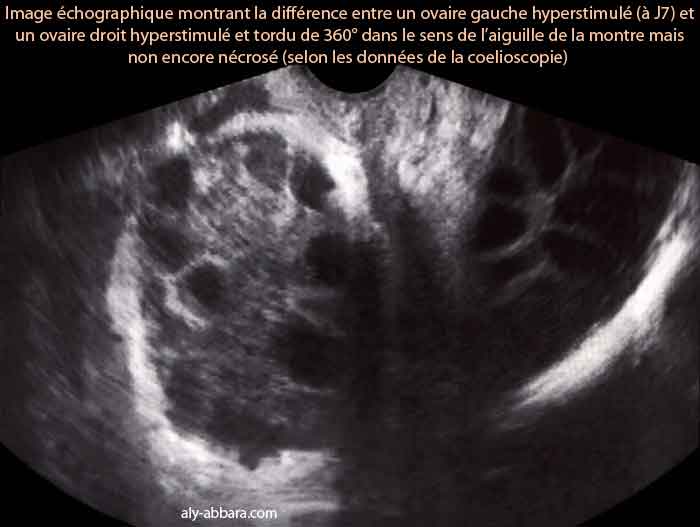

• Cette image échographique montrant les premières modifications affectant l'ovaire suite à une torsion de 360° dans le sens de l'aiguille de la montre, mais sans nécrose (selon les données de la cœlioscopie réalisée 30 minutes plus tard).

• En comparant l'ovaire droit tordu, à l'ovaire gauche non tordu, on peut constater de la présence d'un œdème infiltrant la totalité des structures ovariennes et entraînant l'aspect échographique de l'épaississement du cortex (albuginée) de l'ovaire tordu et de son stroma .